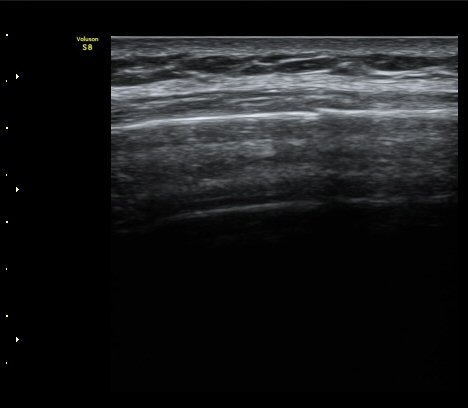

°¥ºñ»À Á¾´Ü¸é°Ë»ç¿¡¼­ °¡°ñ Çü¼ºÀÌ °üÂûµÊ(formation of callus) »çÁø 3